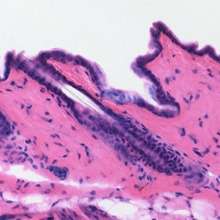

Haematoxylin or hematoxylin (/ˌhiːməˈtɒksᵻlᵻn/), also called natural black 1 or C.I. 75290, is a compound extracted from the heartwood of the logwood tree (Haematoxylum campechianum).[1] Haematoxylin and eosin together make up haematoxylin and eosin stain, one of the most commonly used stains in histology. This type of stain is a permanent stain as opposed to temporary stains (e.g. iodine solution in KI). Another common stain is phosphotungstic acid haematoxylin, a mix of haematoxylin with phosphotungstic acid. When oxidized, it forms haematein, a compound that forms strongly coloured complexes with certain metal ions, the most notable ones being Fe(III) and Al(III) salts. Metal-haematein complexes are used to stain cell nuclei prior to examination under a microscope. Structures that stain with iron- or aluminium-haematein are often called basophilic, even though the mechanism of the staining is different from that of staining with basic dyes.

These stains are commonly employed for histological studies. The mordants used to demonstrate nuclear and cytoplasmic structures are alum and iron, forming lakes or coloured complexes (dye-mordant-tissue complexes), the colour of which will depend on the salt used. Aluminium salt lakes are usually coloured blue-white, whereas ferric salt lakes are coloured blue-black.